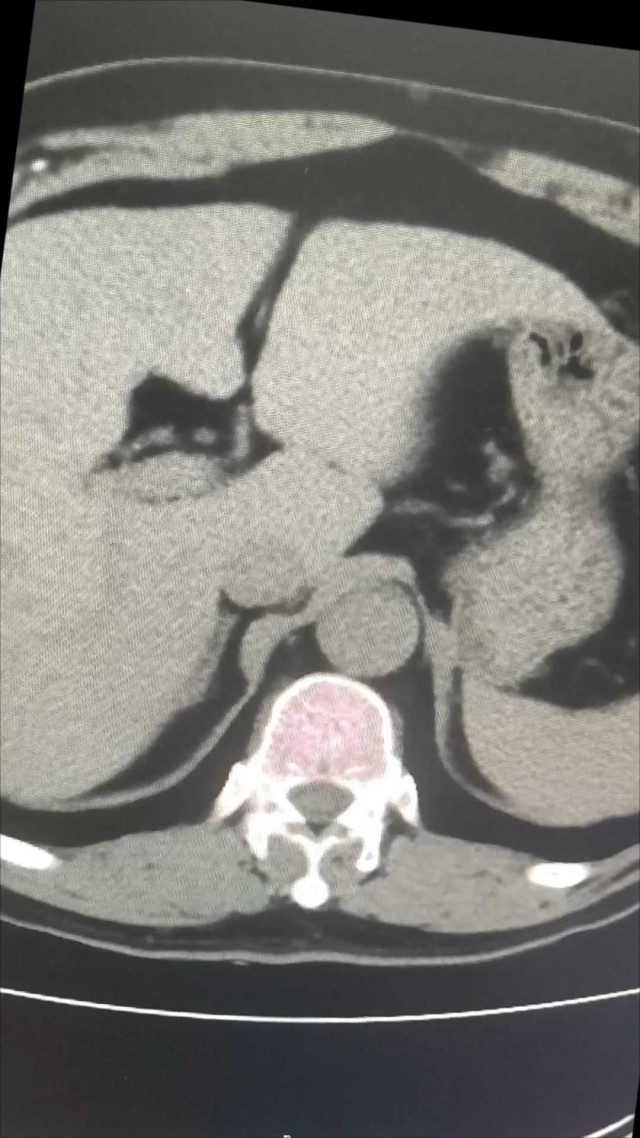

病例信息患者女,33岁,因“反复双乳溢乳4+月,月经紊乱2月”就诊。自述产后2+年,反复出现双乳溢乳2次,再次溢乳4+月。伴双乳头痛,无发热、畏寒,大小便饮食正常。自诉既往月经月经规律,初潮年龄15岁,经期5天,周期28天。近2月月经紊乱,末次月经2025.7.25。1+年前因乳腺脓肿分别在于外院行脓肿切开引流及穿刺置管引流,术后愈合时间均长。4月前于行脓肿穿刺抽脓术,经穿刺抽出约2ml黄色脓液,穿刺液培养无细菌和真菌生长。多次行乳腺彩超示双乳乳腺导管扩张,透声差:BI-RADS3类。两次查泌乳素正常,查性激素、甲功五项正常。垂体磁共振示部分空蝶鞍,垂体未见异常。1天前左侧乳腺肿痛不适,彩超示